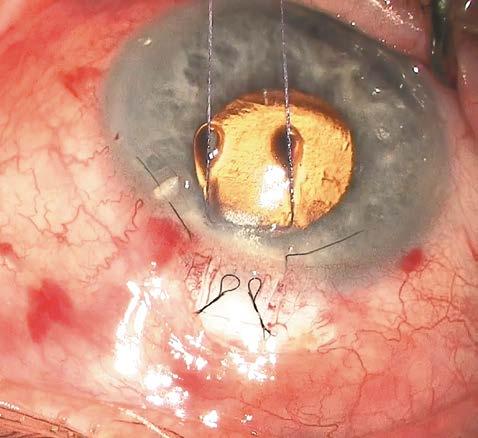

Presentamos el caso de una paciente de 81 años con agudeza visual de ‘cuenta dedos’ en el ojo derecho y antecedente de trabeculectomía, cuya ampolla filtrante superior se encontraba funcional, pero marcadamente adelgazada (Figuras 1 y 2).

A la exploración, destacaba una catarata hipermadura, PIO de 9 mmHg y daño glaucomatoso avanzado (copa/disco 0.9).

La estrategia quirúrgica se definió mediante la microscopia especular y la UBM: un RCE crítico de 997 células/mm² (Figura 3) y un cristalino de gran diámetro anteroposterior con lens vault aumentado (Figura 4).

Figura 1. Catarata hipermadura